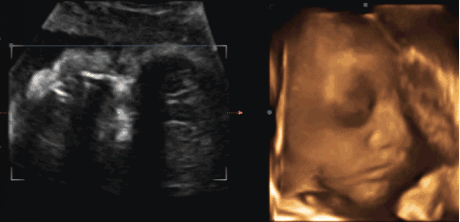

活動(dòng)現(xiàn)場(chǎng),眉山蘊(yùn)纓婦產(chǎn)醫(yī)院運(yùn)營(yíng)院長(zhǎng)趙麗介紹了醫(yī)院整體情況和蘊(yùn)纓5D高清彩超,讓準(zhǔn)爸爸、準(zhǔn)媽媽們更加全面的了解我院產(chǎn)科的特色與5D彩超的優(yōu)勢(shì)。

隨后,在全場(chǎng)準(zhǔn)爸爸、準(zhǔn)媽媽的倒數(shù)計(jì)時(shí)下,幾位領(lǐng)導(dǎo)嘉賓共同啟動(dòng)了蘊(yùn)纓5D高清彩超發(fā)布儀式,這標(biāo)志著蘊(yùn)纓5D高清彩超時(shí)代的到來(lái)!